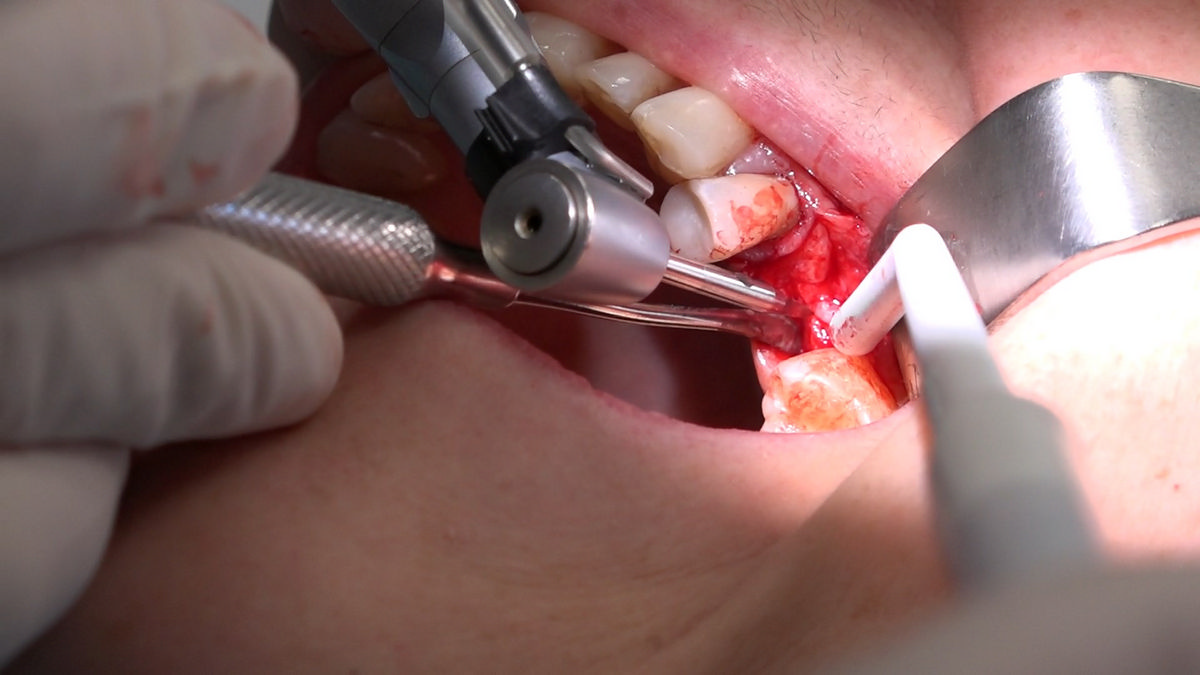

PRACTICULUM IMPLANTOLOGII - SEZON X - SESJA 4 - GRUPA B